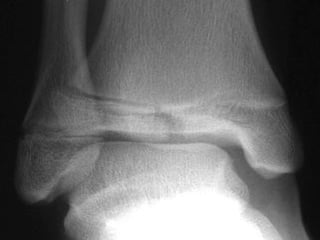

LOCALIZACION Diafisiaria Metafisiaria Epifisiaria Intraarticular Fractura-luxación

LOCALIZACION Diafisiaria MetafisiariaEpifisiaria Intraarticular Fractura-luxación